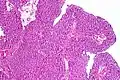

| Histopathology of transitional carcinoma of the urinary bladder. Transurethral biopsy. Hematoxylin and eosin stain. | |

The 1973 WHO grading system for transitional cell carcinomas (papilloma, G1, G2 or G3) is most commonly used despite being superseded by the 2004 WHO[14] grading for papillary types (papillary neoplasm of low malignant potential [PNLMP], low grade, and high grade papillary carcinoma). High-grade carcinoma typically displays more pleomorphism, multiple mitoses, euchromatin and relatively prominent nucleoli, and uneven distribution of nuclei.

Transitional cell carcinoma, being low-grade to the left, and high-grade to the right. H&E stain -

Papillary transitional cell carcinoma, low grade -

Histopathology of urothelial carcinoma of the urinary bladder, showing a nested pattern of invasion. Transurethral biopsy. H&E stain -

Histopathology of urothelial carcinoma of the urinary bladder. -

Micrograph of urethral urothelial cell carcinoma. H&E stain